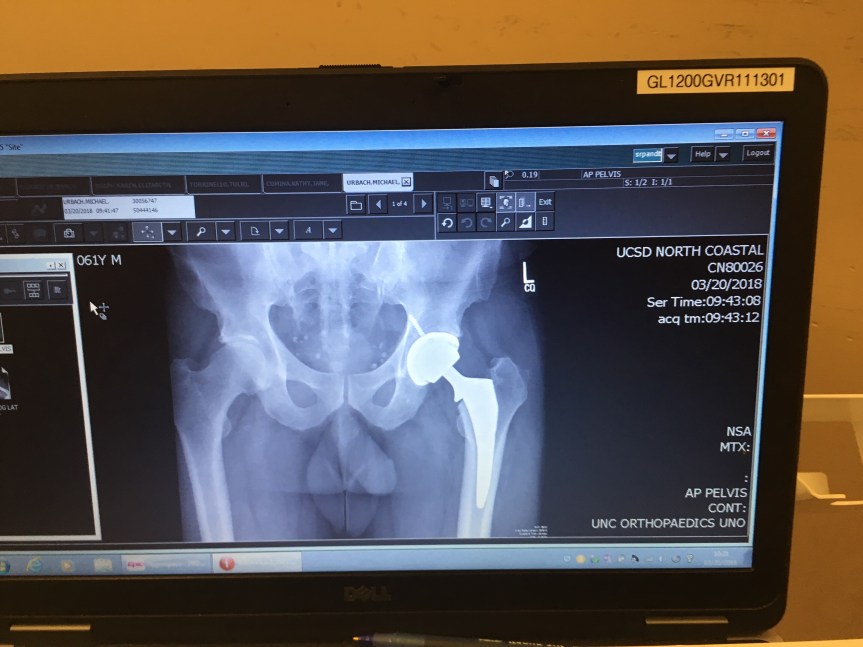

Today marks four weeks post hip replacement. I went in to see the surgeon so he could follow up and see how things are coming along. As usual, it is a long wait. Excellent surgeon, great doctor for talking to you straight, just wish he’d work on the time management side of the business. It’s at minimum an hour past your appointment time before you see him. That said, I’d not go anywhere else to get this operation done. Dr. Ball is the top of the line for orthopedic surgery. I’m doing really good. You wouldn’t have known that the first two weeks when I was totally depressed over being unable to do the simplest things. Of course, it didn’t help that the dog died and my wife is 3000 miles away. Anyway, I can almost put a shoe on and I’m now able to sleep on my side. I can walk without the cane and do 15 minutes on the exercise bike. I got fresh x-rays showing everything looking good and I am cleared to do whatever I can tolerate pain wise. I just can’t turn my leg outward for another month until everything is completely stable.